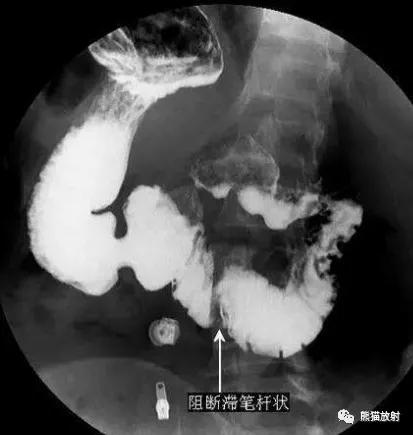

①十二指肠梗阻性表现:钡剂通过十二肠升段受阻,其上扩张。轻者仅为十二指肠舒张,蠕动活跃亢进,逆蠕动多次发生;严重者十二指肠明显扩张,蠕动及逆蠕动频繁,钡剂可反流入胃,甚至出现胃扩张。

②十二指肠升段笔杆状压迹:这一征象并非常见。表现为升段有光滑整齐的纵行压迹,状如“笔杆”,黏膜纹变平。

③体位改变的影响:十二指肠梗阻、淤张现象,常于立位、仰卧位时显著,而于俯卧位、胸膝卧位或向上推压小肠时缓解或消失。